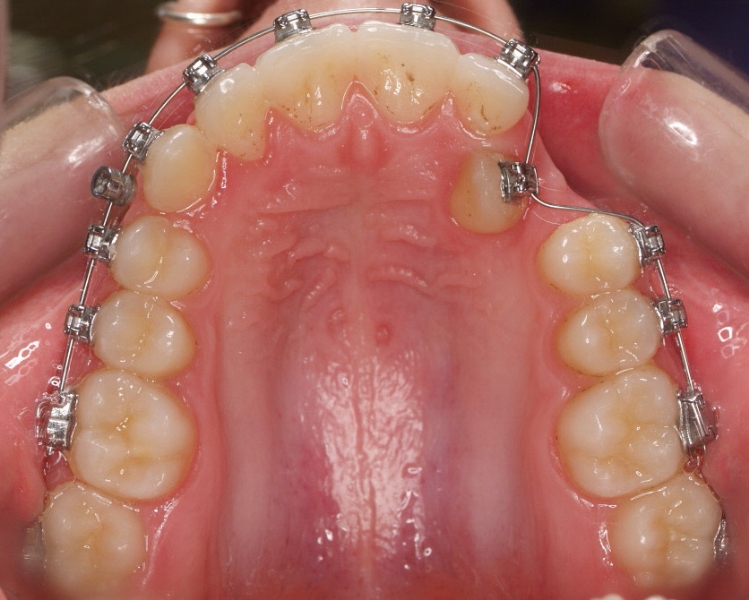

Clase II paciente 15 años

La paciente O.O. acude a nuestra consulta por:

– Canino 13 e incisivo lateral 42 en posición ectópica.

– Canino 23 incluido.

Con lo que decide realizarse un tratamiento de ortodoncia de duración de 24 meses con brackets damon Q.

CASO COMPLETO: